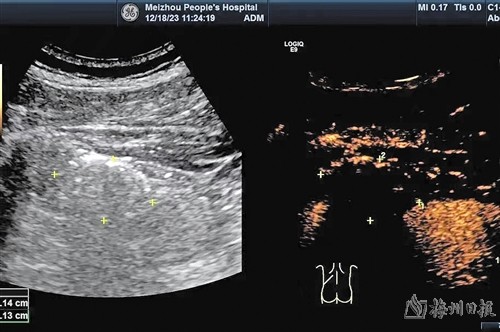

术后即刻超声造影提示:左肾错构瘤被完全灭活。

经过全面的术前评估,蓝思荣副主任带领介入超声团队顺利为患者完成“超声引导下经皮左肾肿瘤穿刺活检+肿瘤微波消融术”,术中即刻超声检查显示:瘤体被完全灭活。病理结果证实为肾错构瘤,术后患者恢复快,顺利出院了。3个月后随访显示,肾错构瘤体积较术前缩小,瘤体内未见残余血供。